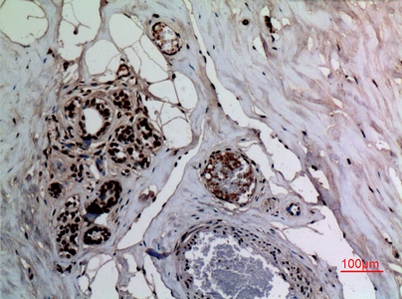

| Dilutions: | Western Blot: 1/500 - 1/2000. IHC-p: 1:100-300 ELISA: 1/20000. Not yet tested in other applications. |